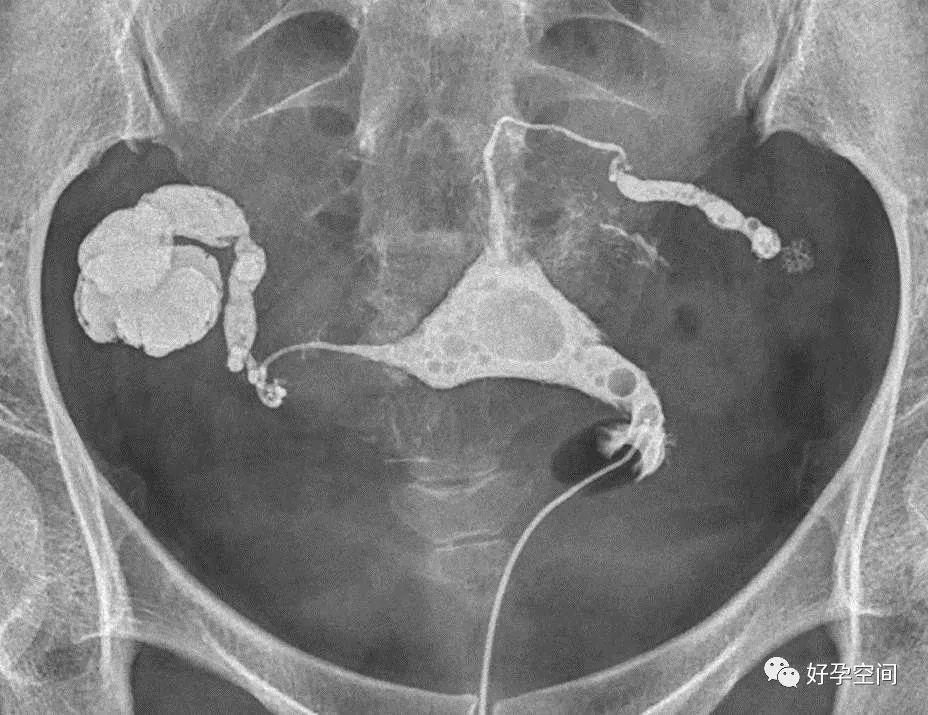

输卵管阻塞,走行僵硬

,功能丧失